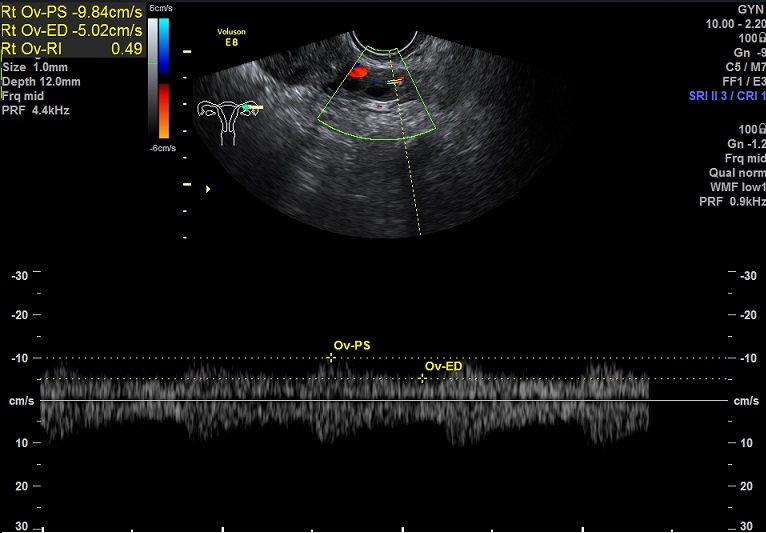

女性,27岁,原发性不孕。

2015-1-12,月经第3天检查

左卵巢: 大小2.9x2.3x1.4cm 体积:4.8 窦卵泡:4个 卵巢间质血流:9.8cm/s RI:0.49

右卵巢: 大小 2.6x1.6x1.3cm 体积:2.8 窦卵泡:2个 卵巢间质血流:11.5cm/s RI:0.52